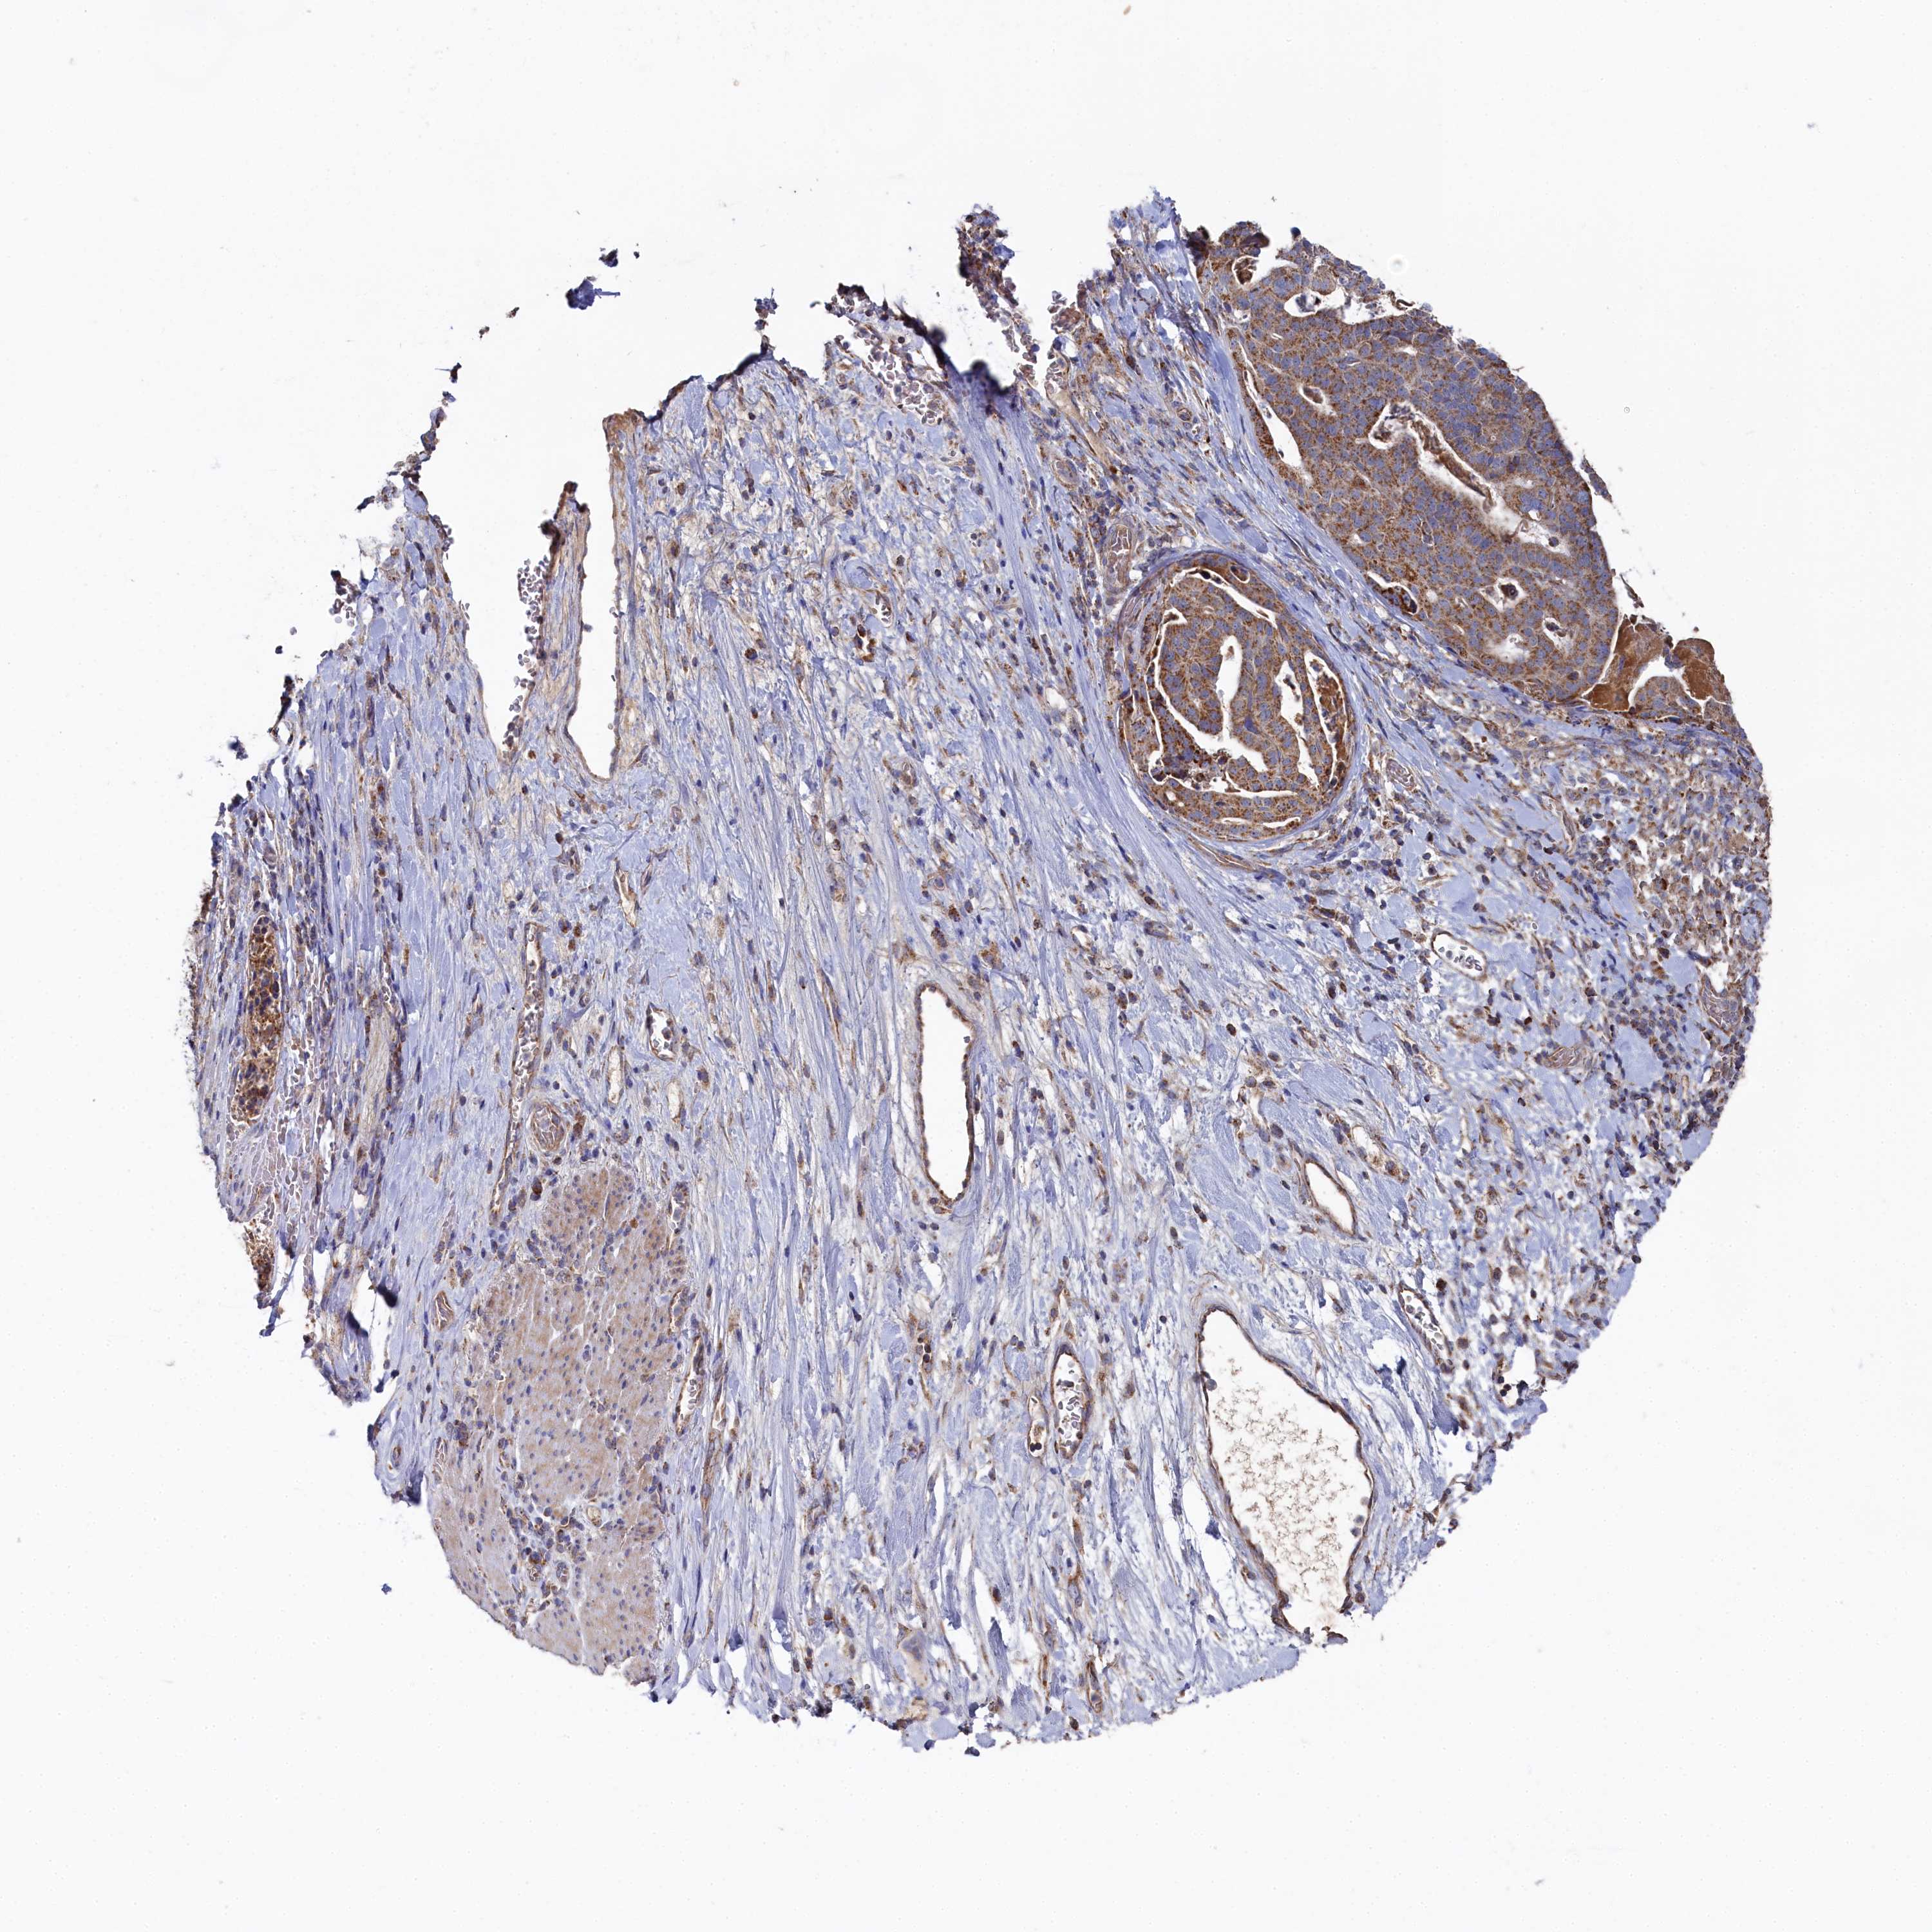

STOMACH CANCER - Protein expressioni

A mouse-over function shows sample information and annotation data. Click on an image to view it in a full screen mode. Samples can be filtered based on level of antibody staining by selecting one or several of the following categories: high, medium, low and not detected. The assay and annotation is described here.

Note that samples used for immunohistochemistry by the Human Protein Atlas do not correspond to samples in the TCGA dataset.

Antibody stainingi

Antibody staining in the annotated cell types in the current human tissue is reported as not detected, low, medium, or high, based on conventional immunohistochemistry profiling in selected tissues. This score is based on the combination of the staining intensity and fraction of stained cells.

Each image is clickable and will lead to virtual microscopy that enables deeper exploration of all samples and also displays staining intensity scores, fraction scores and subcellular localization as well as patient and tissue information for each sample.

Antibody HPA039965

Staining

High

Medium

Low

Not detected

Intensity

Strong

Moderate

Weak

Negative

Quantity

>75%

75%-25%

<25%

None

Location

Nuclear

Cytoplasmic/membranous

Cytoplasmic/membranous,nuclear

Adenocarcinoma, NOS

Adenocarcinoma, High grade